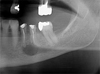

The patient was an 80-year-old woman presenting with a history of coronary stent placement for ischemic cardiopathy, lower left lip in situ squamous cell carcinoma (ipsilateral to the PIOSCC) and a frigore face paralysis. She was treated with acetylsalicylic acid, bisoprolol, glyceryl trinitrate and atorvastatin, was a former smoker and had no allergies. A routine radiographic examination in August 2024 revealed a radiolucent lesion in the left mandibular premolar region (Fig. 1), involving the first and second left lower premolar teeth (20 and 21, using the ADA system). Both teeth had undergone endodontic treatment 10 yr earlier, but a recurrence of apical granuloma was noted on both teeth on the periapical radiograph from May 2024 (Fig. 2). The patient reported no pain, swelling, or any associated systemic symptom.

Fig. 1 Patient dental panoramic before primary attempt of apical cyst enucleation in august 2024. |

During the pre-operative consultation, the panoramic radiography (Fig. 1) revealed an unilocular radiolucent lesion with a major axis of more than 5 mm, located around the roots of teeth 20 and 21, extending toward the inferior alveolar nerve canal. Cone Beam Computed Tomography (CBCT) imaging showed a radiolucent and homogenous oval lesion with regular contours, measuring 10 × 12.7 × 7.5 mm, erasing the mental foramen and the cortical wall (Fig. 3).